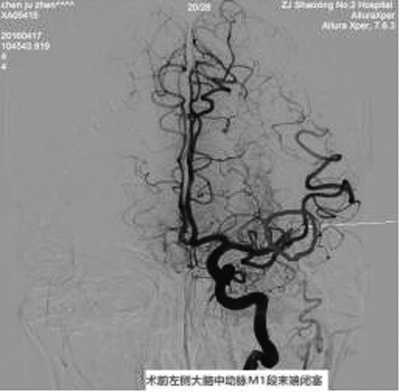

4月17日,我院成功为一位发病1小时到院的急性大血管脑梗死患者联合应用静脉溶栓、动脉内支架取栓、动脉溶栓等多种方法,在发病后3小时19分时开通血管。

该患者4月17日早晨7:30于骑车时突发右侧肢体完全不能活动,跌倒在地,伴言语表达、理解不能,意识模糊。经急诊静脉溶栓、动脉内支架取栓、动脉溶栓、后续康复治疗后,患者已能独立行走,语言理解正常,能部分语言表达。